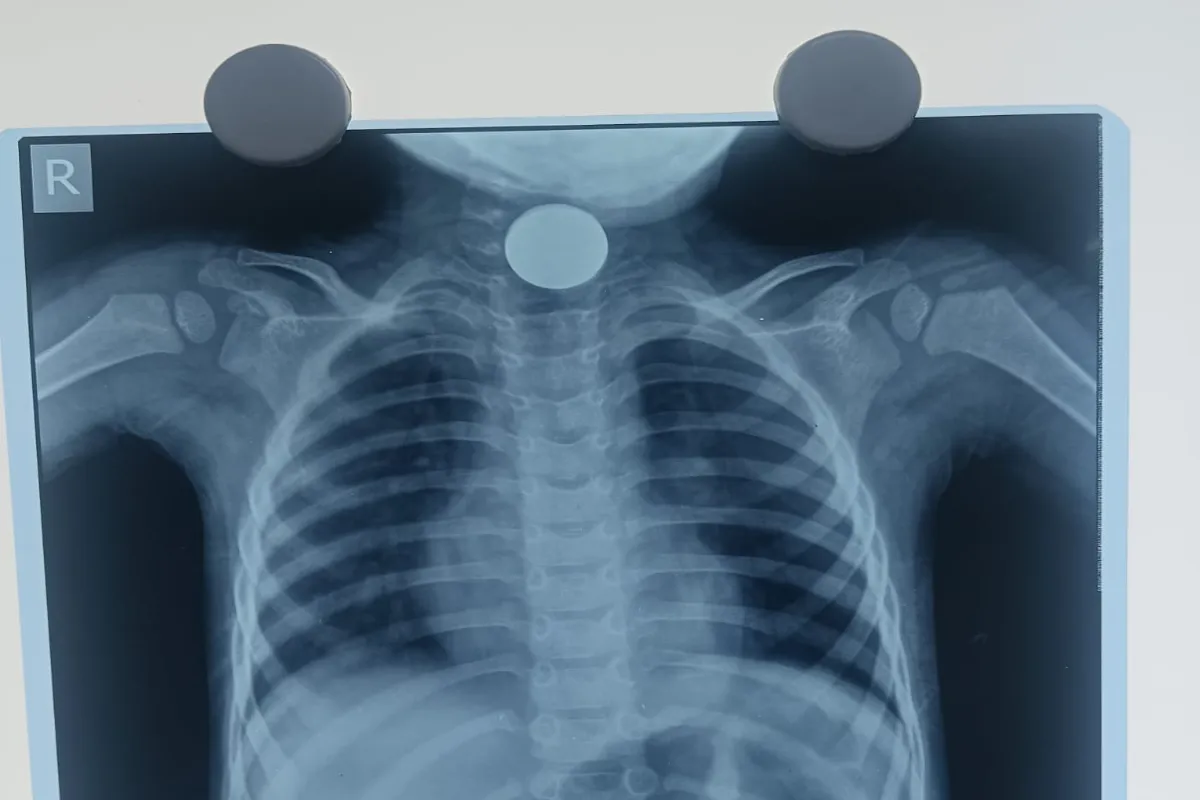

दुमका जिले के गोपीकांदर प्रखंड के रांगा मिशन गांव निवासी एक चार साल के बच्चे राम मड़ैया के गले में 10 रुपए का सिक्का फंस गया था। परिजन को जब इस बात का पता चला तो वे बच्चे को लेकर दुमका के फूलो झानो मेडिकल कालेज अस्पताल पहुंच गए। वहां डॉक्टर्स बच्चे के गले से सिक्का निकालने में असफल रहे। इसके बाद स्थानीय लोग बच्चे को लेकर देवघर एम्स चले गए, जहां डॉक्टर ने बच्चे के गले से सिक्का निकाला और उसने राहत की सांस ली।

देवघर एम्स में ईएनटी विभाग के डॉक्टर शांतनु और उनकी टीम ने बच्चे के गले से सिक्का निकालने की प्रक्रिया शुरू की। डॉक्टर शांतनु ने बताया कि सिक्का बच्चे के गले के बिल्कुल बीच में फंसा हुआ था, जो बच्चे के लिए बहुत गंभीर परेशानी थी। डॉक्टरों ने 15 मिनट के अंदर बच्चे के गले से सिक्का निकाल दिया। इसके बाद परिजनों के आग्रह के बाद बच्चे को अस्पताल से डिस्चार्ज कर दिया गया।